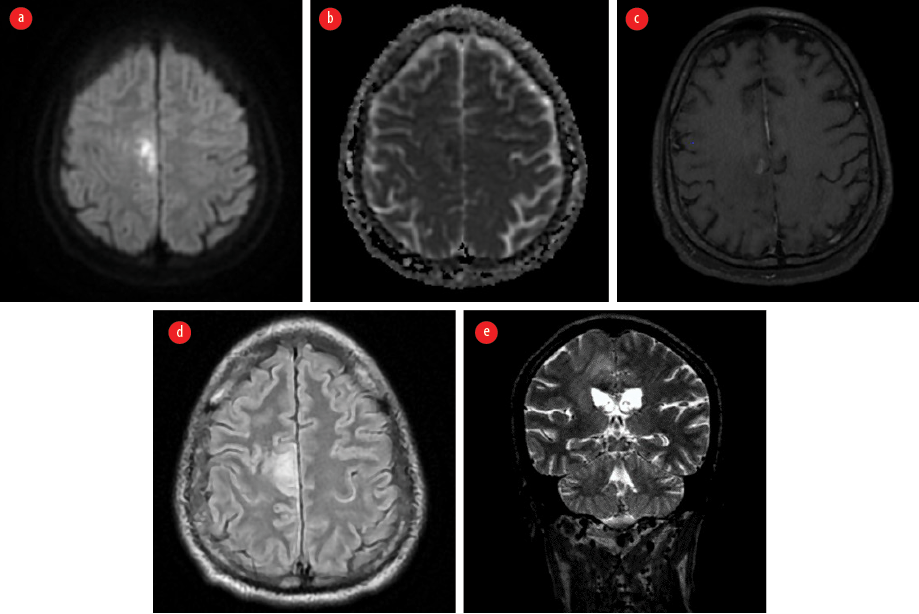

The patient appeared emaciated with a body mass index of 19.8 kg/m2. He was febrile and had right knee joint arthritis. An immediate non-contrast-enhanced magnetic resonance imaging (MRI) brain showed areas of patchy diffusion restriction with corresponding low apparent diffusion coefficient values in the right frontoparietal cortex. Surrounding T2 fluid attenuated inversion recovery hyperintensity suggestive of edema was present in the adjacent white matter with extension to the thalamocapsular region [Figure 1].

Figure 1: Contrast-enhanced MRI of the brain taken on the first visit. (a) Axial diffusion-weighted image shows areas of diffusion restriction in the right frontoparietal cortex. (b) Corresponding apparent diffusion coefficient map indicates the hypointense areas in the involved region. (c) Axial post contrast T1 image shows patchy contrast enhancement in involved area. (d) Axial T2 fluid attenuated inversion recovery image reveals the surrounding edema. (e) Coronal T2 image shows the edema extending to the thalamocapsular region.